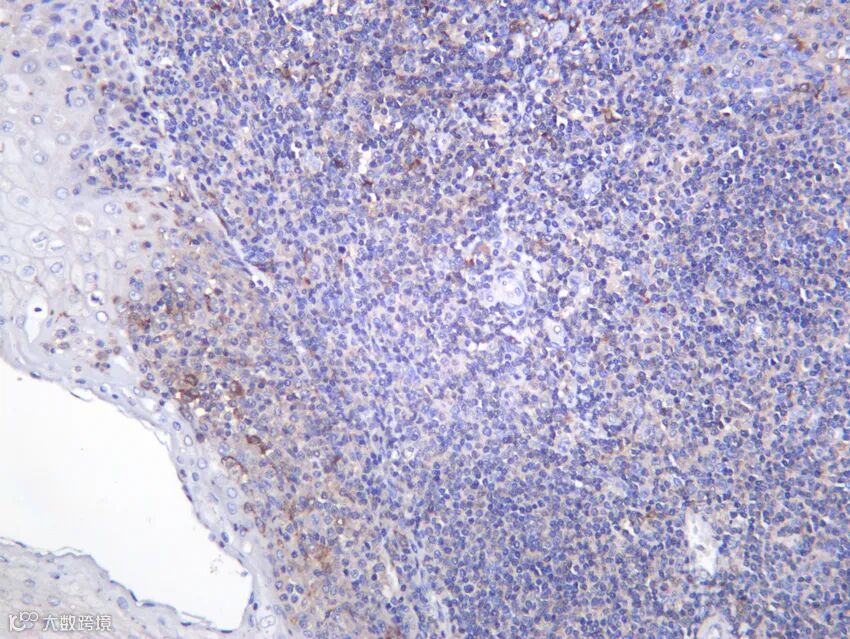

Cbl(Casitas B-lineage lymphoma)是 RING 型 E3 泛素连接酶,通过泛素化修饰活化的受体酪氨酸激酶(如 EGFR、c-Met、PDGFR)及其下游适配蛋白,促进其内吞与溶酶体降解,从而负调控生长因子信号。Cbl 功能缺失突变见于髓系白血病和实体瘤,导致信号通路持续激活。本抗体跨物种识别 Cbl 全长蛋白,支持 IP 验证其与底物互作,是 RTK 信号调控研究的核心试剂。